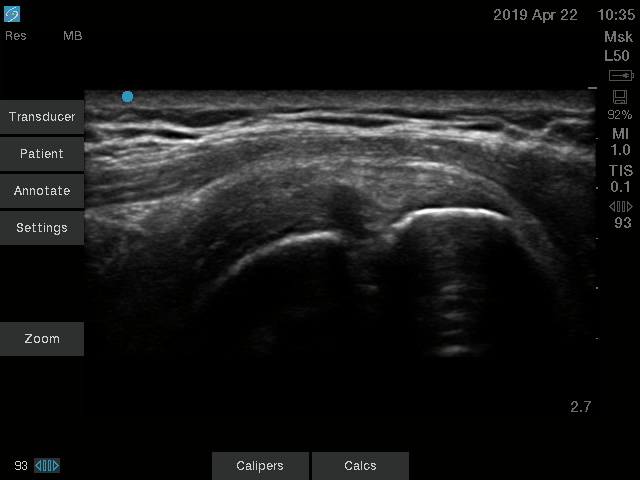

Shoulder Supraspinatus Long Axis Tear Image